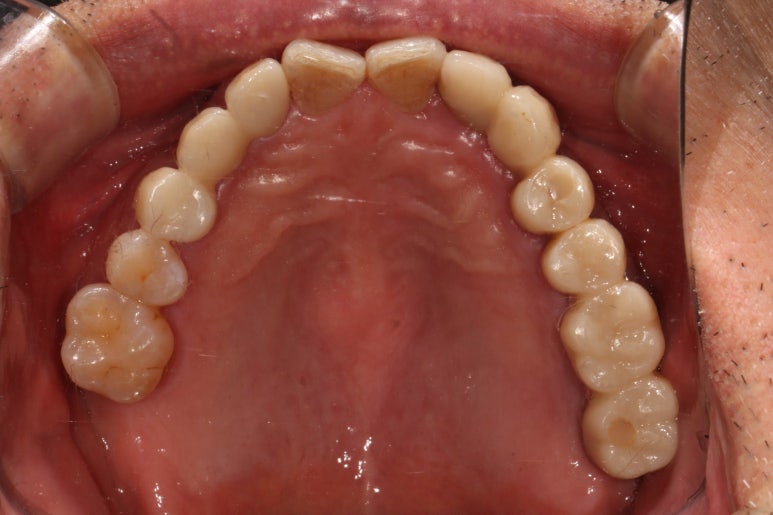

1주일 뒤에 제작된 앞니 지르코니아 브릿지입니다.

제가 봐도 좀 잘되었다고 감히 말할 정도로 완벽한 모습입니다....

사실 딱 보면 브릿지인지도 잘 모르겠네요...

고개를 돌려 확인해보면 더더욱이 감탄이 나오는데요...

바로 요기가 새로 제작한 지르코니아 앞니 브릿지입니다.

감쪽같은 앞니 치료 아니겠습니까!! 크... 제가 봐도 칭찬합니다.

입천장에서 바라보면 이제 가지런히 정렬되어있는 치아의 배열을 보실 수 있으실겁니다.